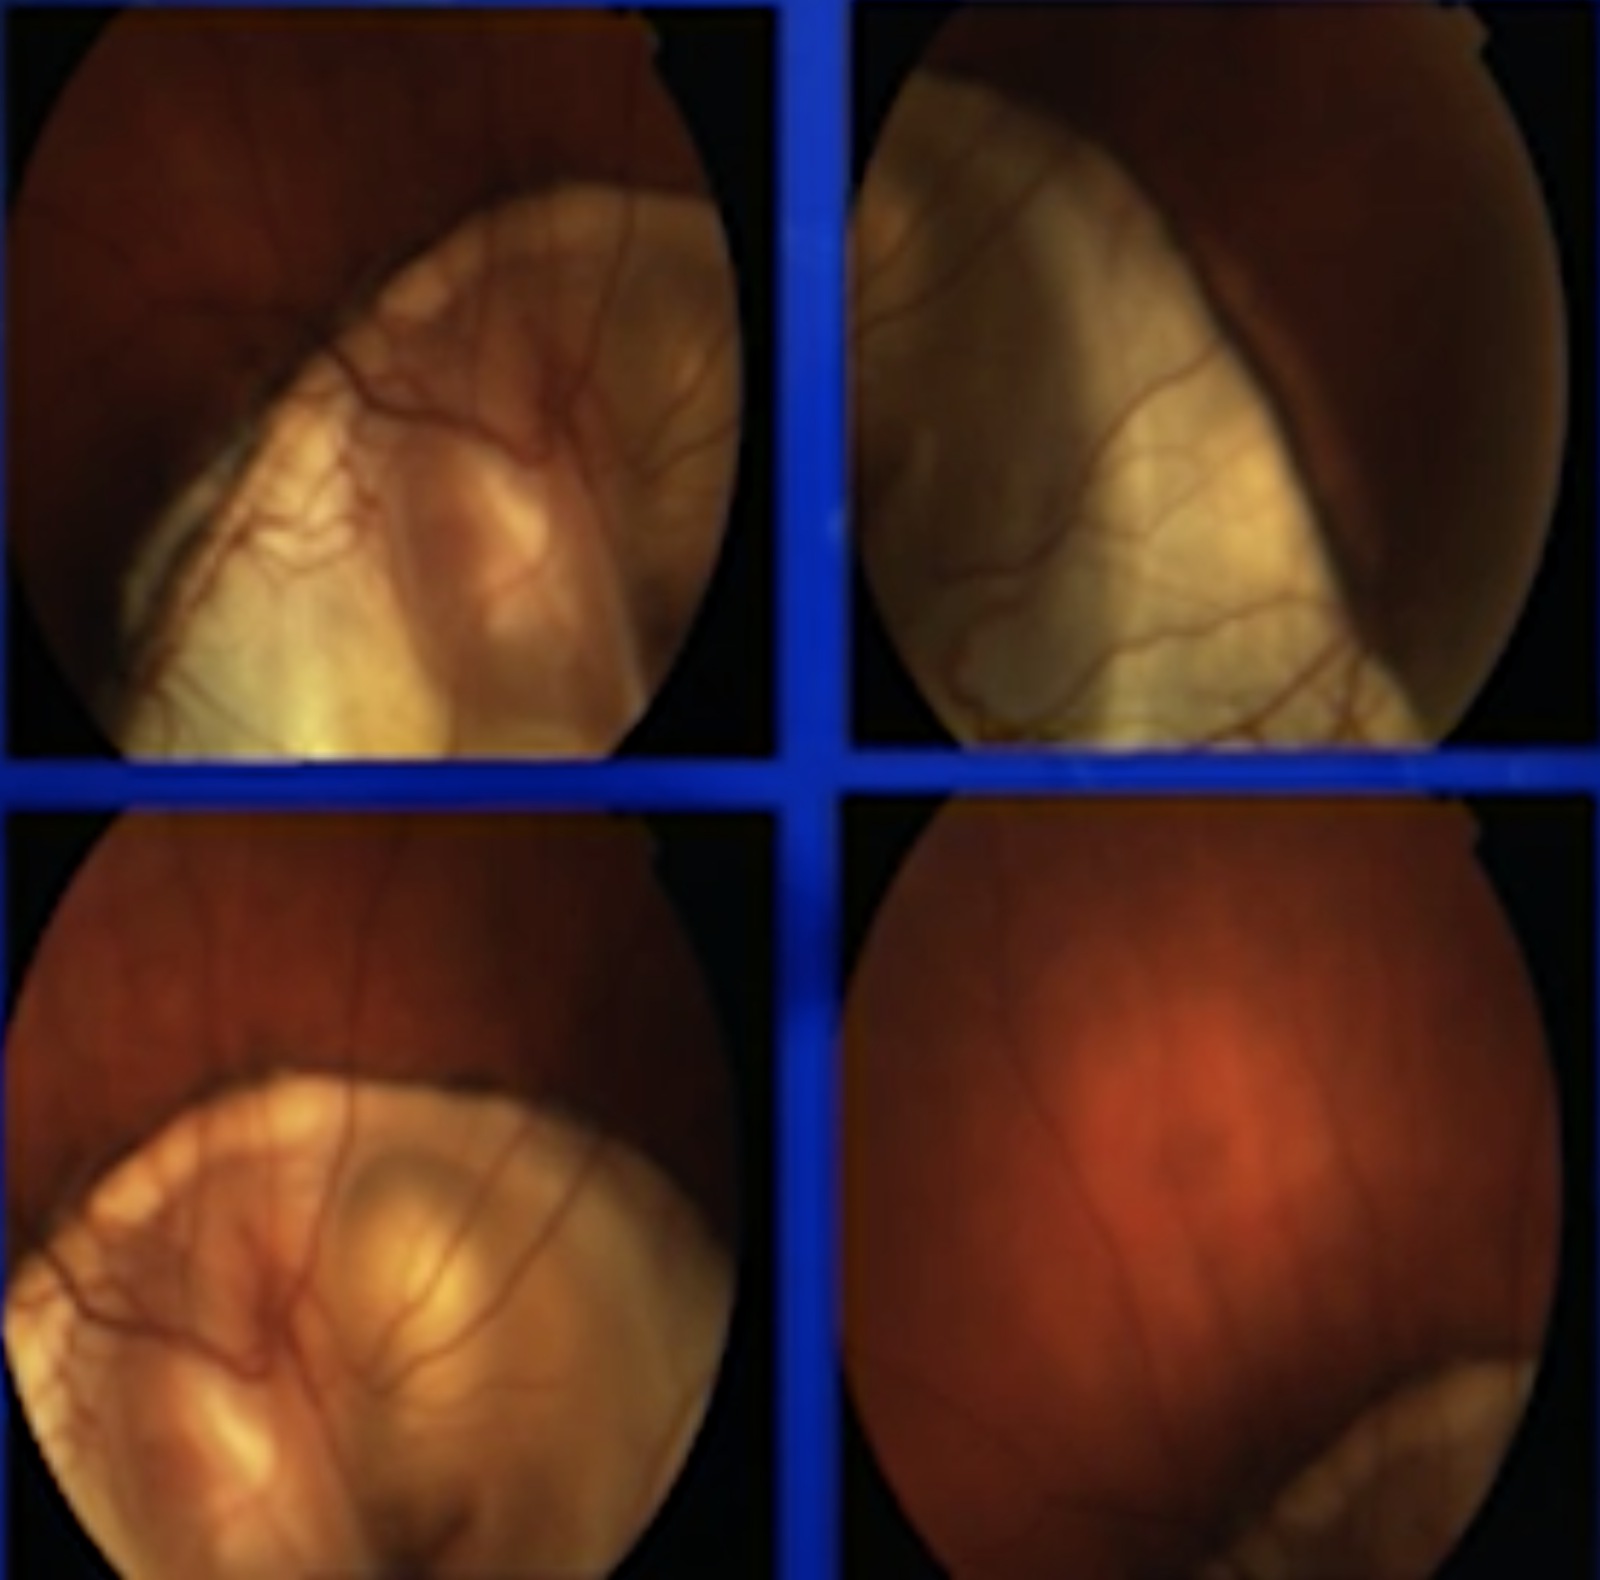

Explore what retina specialists see in the OR by watching videos in an immersive 3D experience.

Stanislao Rizzo, MD

Hudson de Carvalho Nakamura, MD

Frederic Aissani, MD

Manish Nagpal, MS, DO, FRCS(UK)